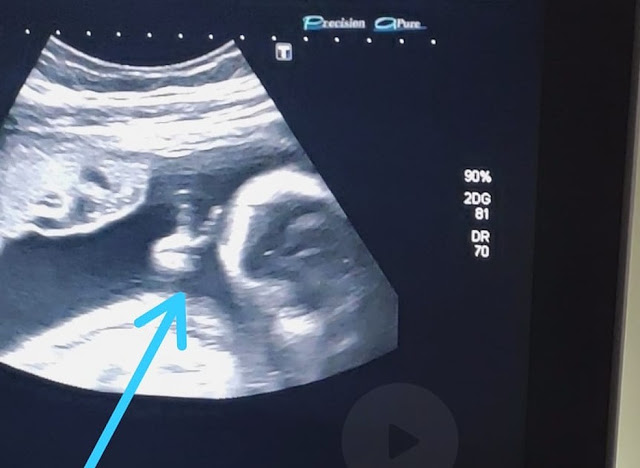

O rapaz conta que ver o ultrassom já é bem emocionante, porque consegue observar como o bebê está e ouvir seu coraçãozinho. Mas, desta vez, ele se deparou com a surpresa de ver o filho Davi fazendo um sinal de 'V' com uma das mãozinhas. “Até a médica falou: 'olha, ele fez o sinalzinho de vitória com a mão'. Eu fiquei sem acreditar”, afirma. Ele encara a situação como um sinal divino de que vai conseguir superar o tratamento e vencer a doença.

“O filho que eu pedi para Deus foi para superar tudo isso que estou passando. Esse sinal foi para fechar com chave de ouro, para eu ter certeza que vou vencer. Se não tivesse ido, não teria visto isso, porque minha mulher não ia conseguir gravar. Aí, eu vou para o ultrassom e tem um sinal desse, parece que é para a minha fé aumentar. Me dá mais força para poder vencer o câncer. Com certeza, foi um sinal divino”, finaliza.